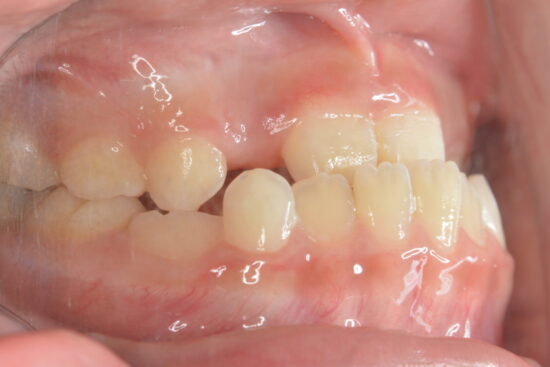

まだ全て乳歯。これより大きい大人の歯がはえてきたらガタガタになるのは確定?と心配なお母さん多いです。